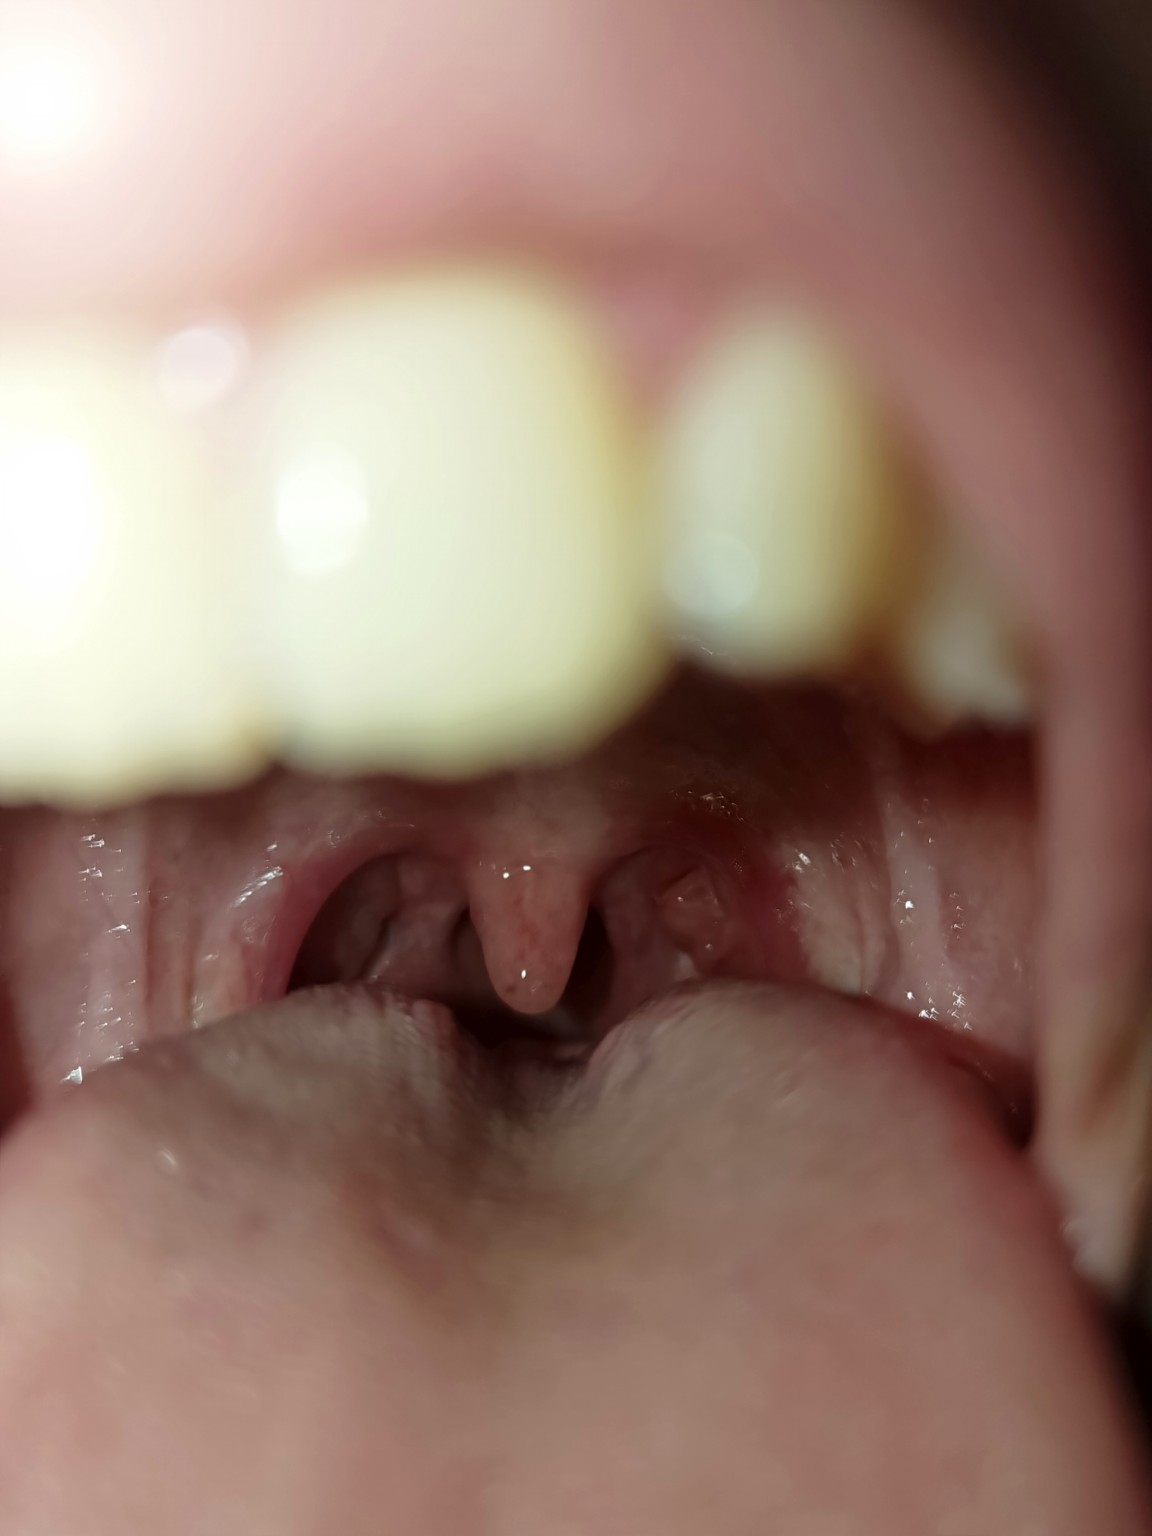

На вашей фотографии:

* На миндалинах нет явных язв или глубоких некротических изменений.

* Налет, если он и есть, не выглядит как плотный, трудно снимаемый некротический налет.

* Обе миндалины выглядят воспаленными, что больше характерно для обычного тонзиллита.

Таким образом, основываясь только на этом изображении, вероятность некротической ангины крайне мала. Гораздо более вероятно, что это обычный острый тонзиллит (ангина) или фарингит.